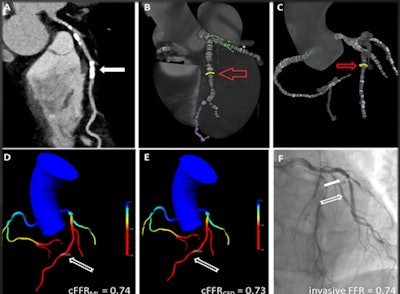

Based on this information, the researchers decided they wanted to see how well a machine learning approach to FFR-CT analysis, which they called cFFRML, compared with a more traditional FFR-CT approach based on analysis of computational flow dynamics (cFFRCFD).

The cFFRCFD algorithm, a research prototype from Siemens Healthineers, is based on a coronary artery model with patient-specific boundary conditions including blood pressure, heart rate, and left ventricular mass, per research by Itu et al. Meanwhile, the cFFRML algorithm uses a deep learning framework to compute the functional severity of lesions; it is trained to utilize a large database of synthetically generated coronary anatomies and their corresponding homodynamic conditions from a computational fluid dynamics simulation.

Albrecht and colleagues compared the performance of both techniques on a per-lesion and per-patient basis. They also visually graded stenoses on CCTA, invasive coronary angiography, and invasive fractional flow reserve as the gold standard.

On a per-lesion basis, the machine learning algorithm delivered the same sensitivity as traditional fractional flow reserve (77%), but the machine learning algorithm's specificity was a little higher, at 96% versus 94% for fractional flow reserve. Even so, the per-lesion analysis revealed no differences in accuracy between the two algorithms, Albrecht said.

Additionally, a Bland-Altman analysis showed no systemic bias, with a mean difference value for both cFFRML and cFFRCFD of 0.003. The Pearson's correlation coefficient for both cFFRML and cFFRCFD with invasive FFR was r = 0.68 (p < 0.0001).